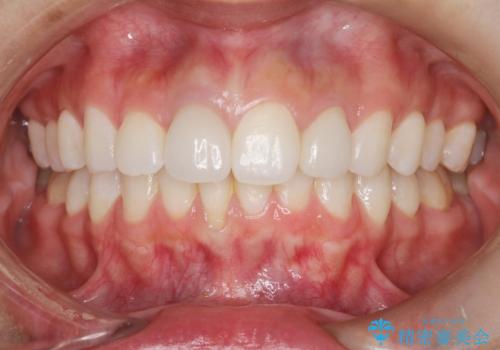

- 以前、上下左右4本抜いてワイヤー矯正をしていた方で、後戻りで下の前歯のガタガタを気にして来院されました。

マウスピース矯正にて、下の歯はIPR(歯と歯の間を削る)を入れることでガタガタの改善、咬み合わせの深さも改善をはかる治療計画をたてました。

歯と歯の間を削って隙間を作って矯正をしています。

保定装置(後戻り防止のための装置)は、基本的にはマウスピースタイプをお渡ししているのですが、患者様のご希望で取り外ししないタイプを希望されたので、前歯の裏側を細いワイヤーで固定(ボンディングリテーナー)を作成しています。